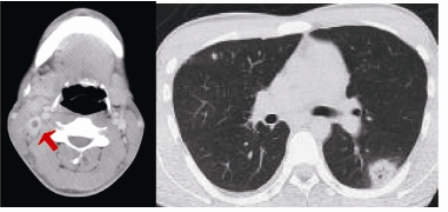

アンピシリン・スルバクタムによる治療を開始した。3日後に血液培養からFusobacterium necrophorumが検出されてきたため、ペニシリンG+クリンダマイシンに変更し、4週間の治療を行った。咽頭スワブ、喀痰培養は陰性であった。各種ウイルス抗体検査は陰性であった。解熱までには約1週間を要したものの、患者は順調に回復した。肺野の結節影はほとんど消失したが、退院直前の頚部エコーでは内頚静脈は閉塞したままであった。約1か月間の治療の後に退院となり、以降再発は認めていない。入院後に撮影されたCT画像を下に示す。

頚部造影CT 胸部CT

赤い矢印は内頚静脈血栓塞像